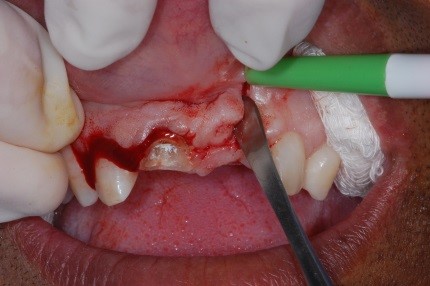

- Figura 9 – Descolamento do retalho.

- Figura 10 – Corte do ápice radicular com broca de alta da série 700.